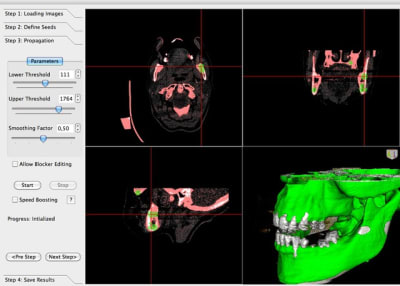

voila mon essaye d'extraction de dent sur Mialite

l'intervalle des densités que j'ai choisie est

Lower Threshold 111

Upper Threshold 1764

mais ce n'est pas reproductible; ça marche pas dans tout les coups